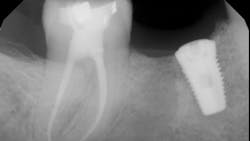

- The type of endodontic treatment dictates the length of healing. Nonsurgical endodontic treatment has a usual healing time of three months. Surgical intervention such as an apicoectomy due to large lesion size can take six to 12 months to heal (figures 1 and 2).

If definitive crown placement is delayed and the patient has excessive forces on the tooth or suffers from direct trauma, the tooth can fracture. In many cases, a decision must be made upon full bone healing versus the likelihood of crown fracture (figure 3–6). In addition, most studies show that full-coverage crowns are a main factor in determining long-term success of root canal therapy, with successes ranging from 92% for teeth receiving crowns compared to 35% for those not receiving crowns after a one- to five-year follow-up.2 In another study on molar teeth five years after root canal therapy, teeth that had crowns placed had a success rate of 78% versus 36% without crown coverage.3